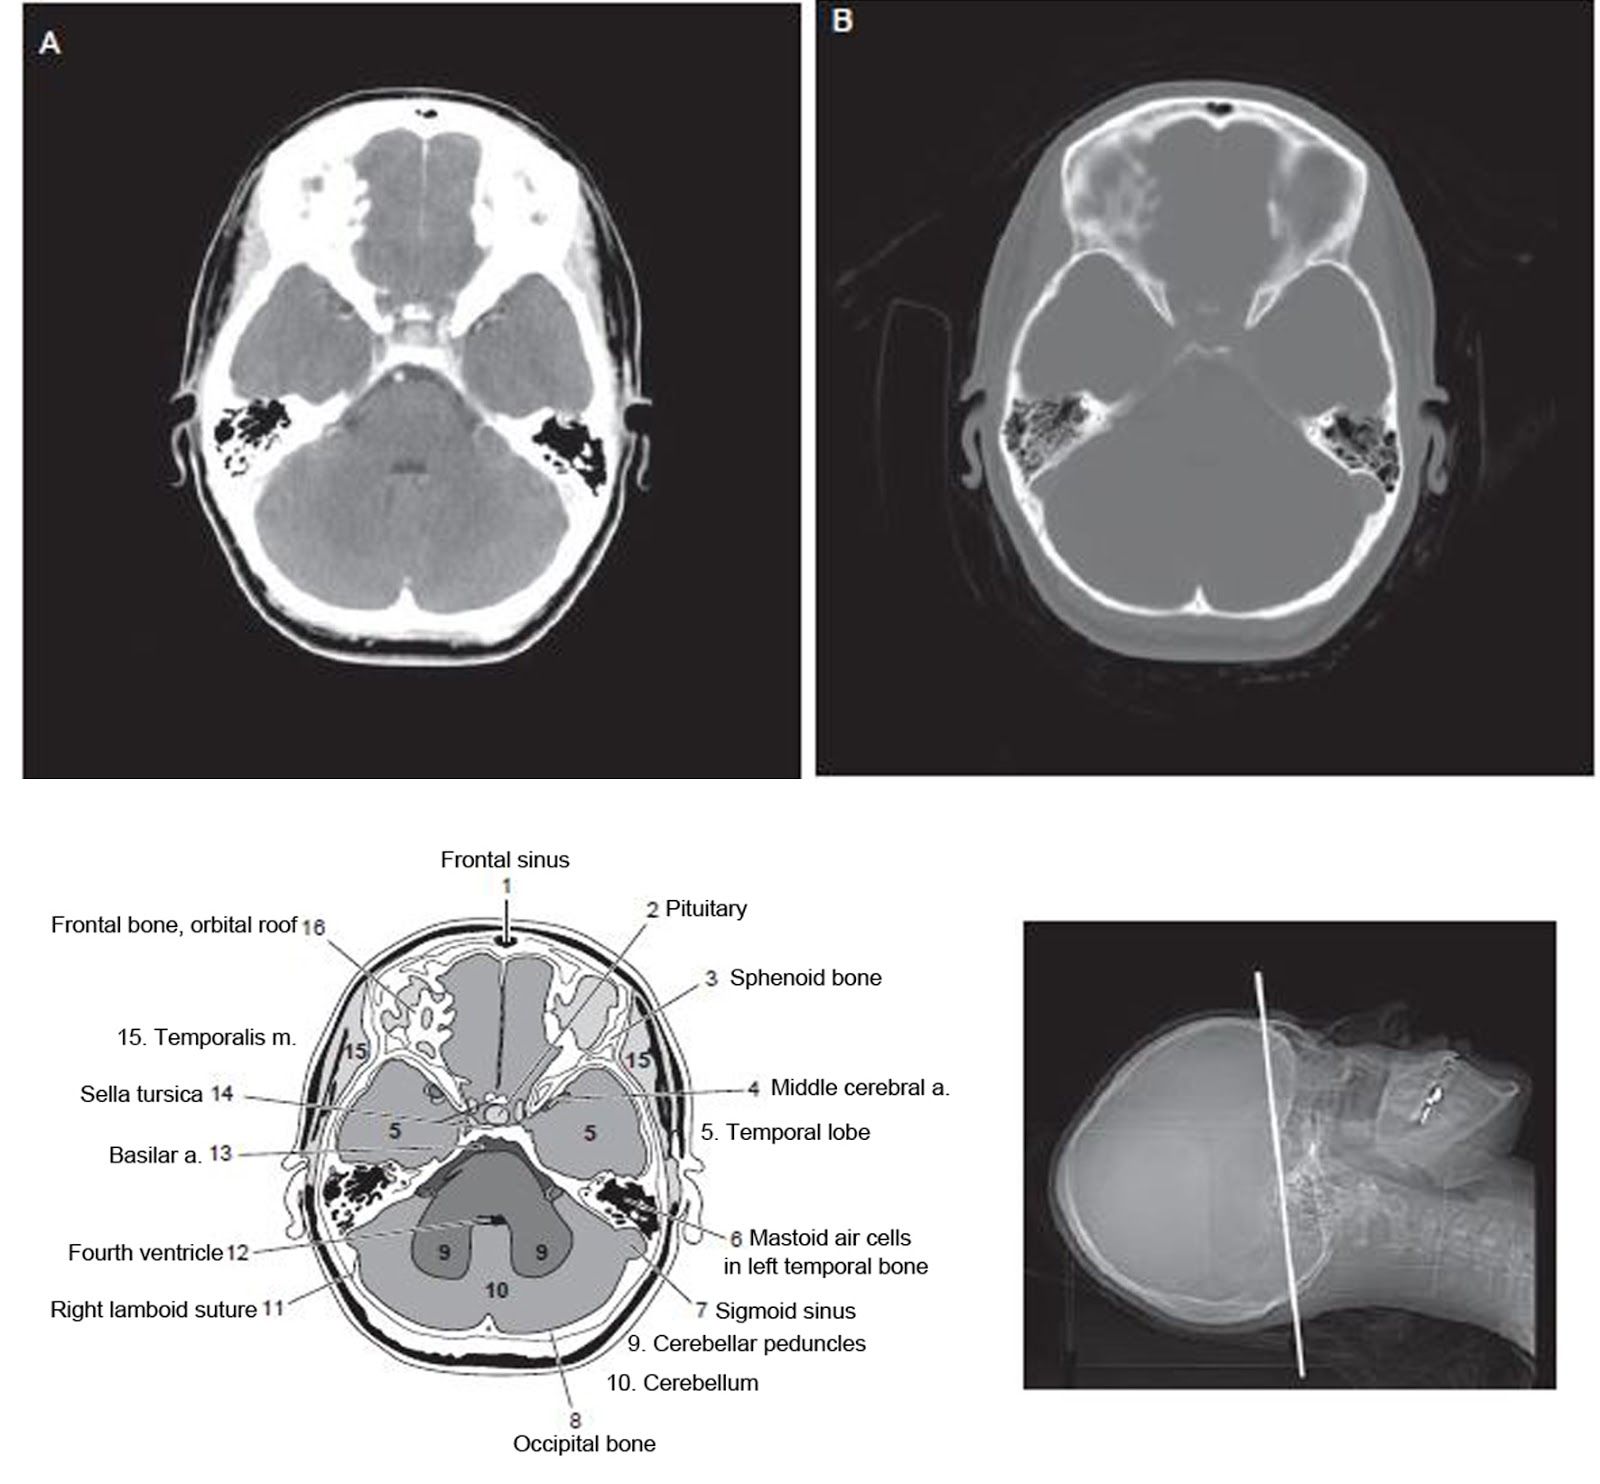

Normal Ct Brain

Normal Brain Ct Anatomy What Is The Purpose Of A Brain Ct Scan why might i need a ct scan of the brain? ct scans may be used to diagnose headaches when neuroimaging is indicated and mri is not available, or in emergency settings when hemorrhage, stroke, or. a cranial ct scan is a diagnostic tool used to create detailed pictures of features inside your head, such as your skull,. What Is The Purpose Of A Brain Ct Scan.

Ct Scan Brain Anatomy Anatomy Of Head Ct Scan Normal The Brain On Ct What Is The Purpose Of A Brain Ct Scan why might i need a ct scan of the brain? a ct (computed tomography) scan is an imaging test that helps healthcare providers detect diseases and injuries. a cranial ct scan is a diagnostic tool used to create detailed pictures of features inside your head, such as your skull, brain, paranasal. ct scans may be used. What Is The Purpose Of A Brain Ct Scan.

Normal Ct Brain What Is The Purpose Of A Brain Ct Scan A ct scan of the brain may be used to check the brain for the following: a cranial ct scan is a diagnostic tool used to create detailed pictures of features inside your head, such as your skull, brain, paranasal. why might i need a ct scan of the brain? a ct (computed tomography) scan is an. What Is The Purpose Of A Brain Ct Scan.